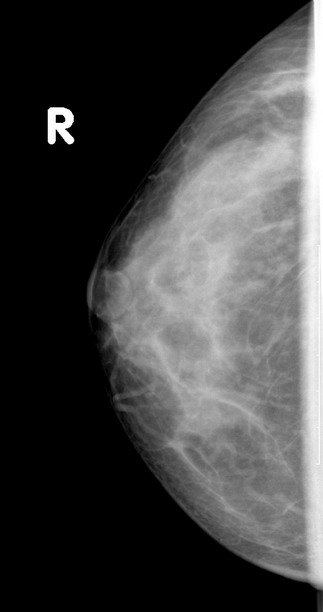

标题: x2364:女,45岁,乳房胀痛,触及硬块求诊 [打印本页]

女,45岁,乳房胀痛,触及硬块求诊

体查:左侧乳房可触及多个硬块,活动度可,无压痛

本人对于乳腺在太多的拿不准,发现乳腺太难看了,我的意见是:

1,左侧乳腺外上象限肿块样影,腺体增生?乳腺纤维瘤?

2,右乳外下象限局部密度增高明显,建议必要时彩超检查除外其他。

3,双侧乳腺小叶增生。

乳头稍凹陷,乳晕皮肤增厚,乳腺非对称性致密,未见明显肿块影,未见异常粗大血管和淋巴结

考虑双侧乳腺小叶增生症.

乳腺非对称性致密,未见明显肿块影,未见异常粗大血管和淋巴结